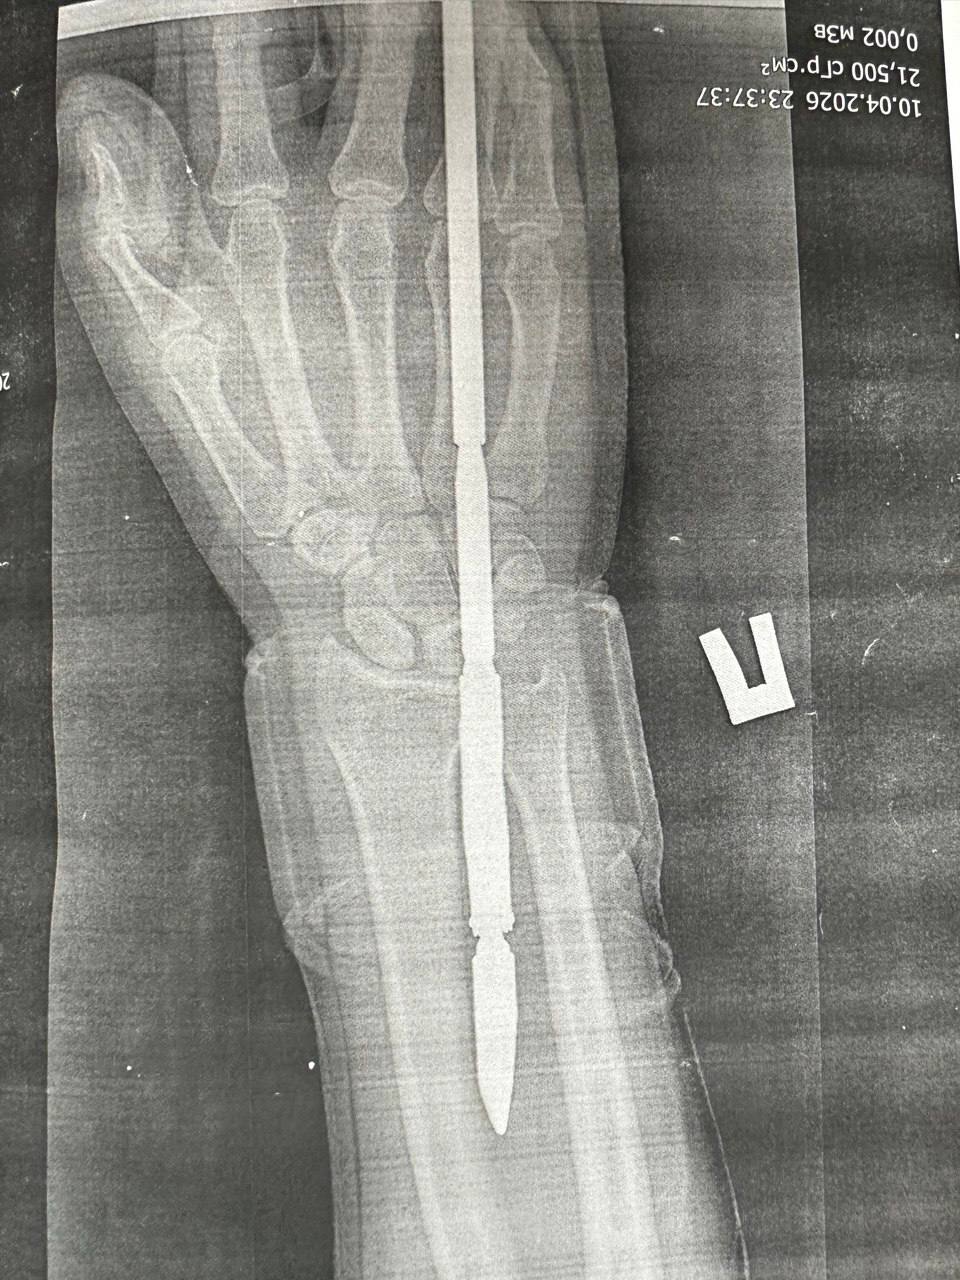

Подводная охота с риском для жизни: орчанин выстрелил себе в руку гарпуном

В отделение травматологии и ортопедии городской больницы Орска поступил 29-летний мужчина с необычной травмой — он загарпунил себя во время подводной охоты. Несчастный...